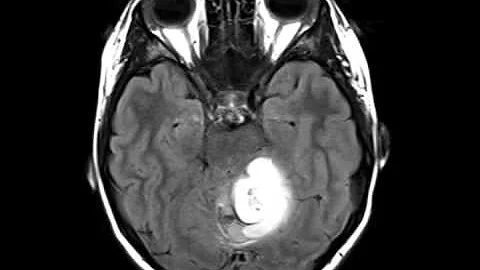

Pilocytic Astrocytoma - Andrew Mork's Mayo Clinic Story - Part 1

Andrew Mork had just joined the Air Force in August 2008 when he began to experience symptoms from a rare tumor of the brain ...